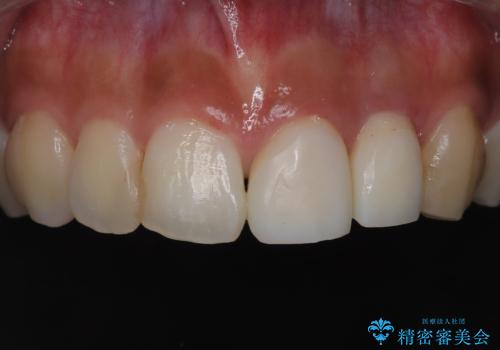

前歯の歯茎の黒ずみと被せ物の形と色が気になる【オールセラミッククラウン】

- 前歯の歯茎の黒ずみと被せ物の形と色が気になるを主訴に来院された患者さんです。精密根管治療とファイバーコア、オールセラミッククラウンで治療を行いました。

歯茎の黒ずみに関しては被せ物と歯の適合が悪く歯の土台の色が見えていました。歯の土台には金属のメタルコアが使用されていたため、根っこの治療の精密根管治療、白い土台のファイバーコア、オールセラミッククラウンで治療を行い歯茎の黒ずみと被せ物の改善を行いました。